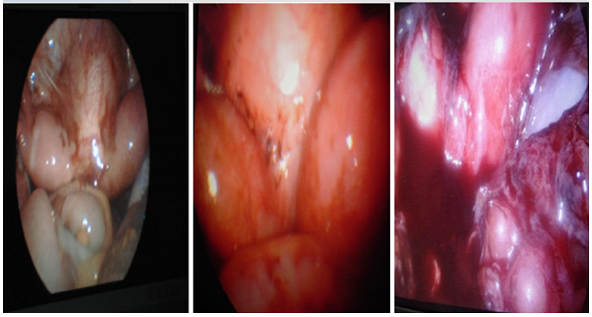

En los tres casos se realizó hemivaginectomia más drenaje de tumor por colección a nivel del segmento vaginal obstructivo y resección del tabique vaginal longitudinal dejando un solo canal vaginal previo abordaje laparoscópico que confirmo presencia de útero didelfo con contenido hemático abundante, libre en cavidad pélvica (hemoperitoneo) y focos de endometriosis, además de hematosalpinx y síndrome adherencial (Fig. 5), permitiendo así por vía laparoscópica corregir las complicaciones asociadas.

Debido a la posibilidad de otras alteraciones en el riñón contralateral, se realizó gammagrama renal en todas las pacientes confirmándose así exclusión renal ipsilateral al hemisistema obstruido y morfo funcionalismo renal normal contralateral. Entre las complicaciones que se presentaron al abordar quirúrgicamente a estas pacientes se encontraron: endometriosis en pelvis, abdomen, hemoperitoneo y síndrome adherencial en dos de las tres pacientes y hematosalpinx en una de ellas; esto concuerda con lo reportado en la mayoría de las publicaciones (17,18,19,20,21,26) requiriéndose realizar ablación y cauterización de focos endometriosicos, succión aspiración del hemoperitoneo y adherensiolisis, con la finalidad de resolver las complicaciones asociadas al síndrome de HWW (OHVIRA).